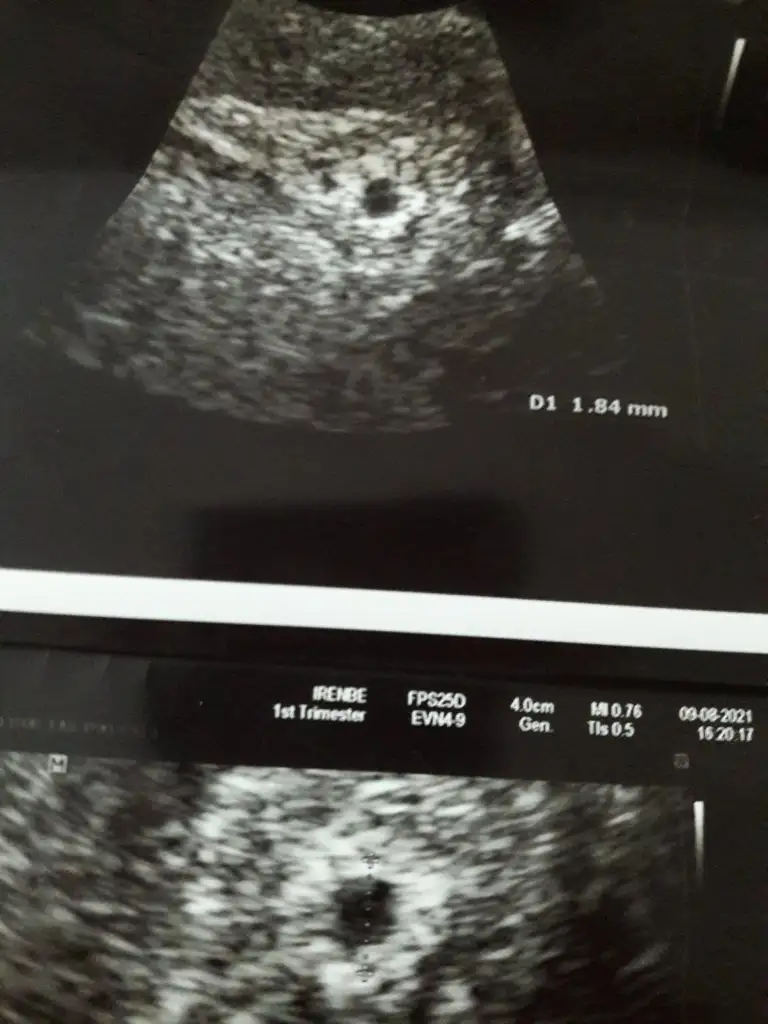

Amin canım dualarım hepimiz için benim ultrasona bakarmisin 5+2 mi anlamadım yolk keseside 1.84mm . 2.5 in altı sağlıksız gebelik sayılıyormus öyle okudum bi yerde😔

5 hafta 2 günlük kuzum kese 4cm yolk 1.84 mm oda 5 haftalık gebelik için gayet normal